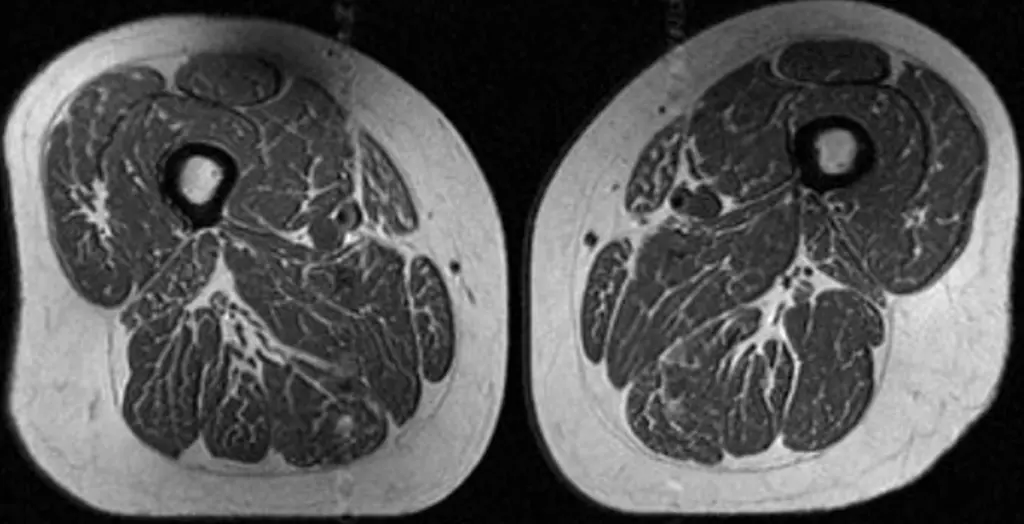

Ultraprocessed foods are turning human thighs into well-marbled steaks

Ultraprocessed food intake was linked to more thigh muscle fat on MRI in a new study. Learn how diet may affect muscle quality and knee health.